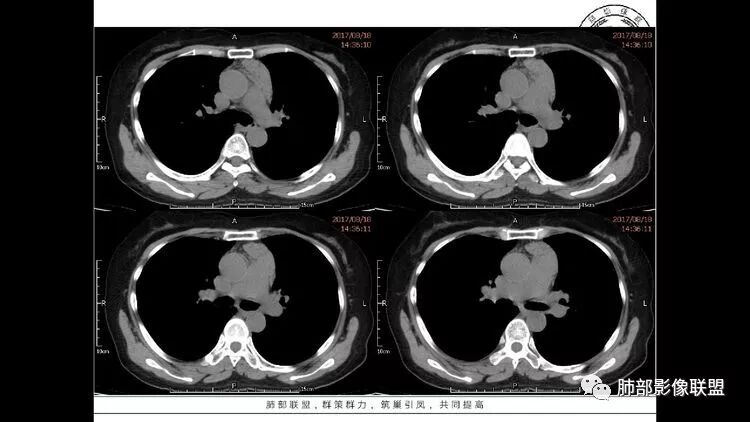

3.纵隔淋巴结肿大?,以主动脉弓为界向上向下增大。

中年女性,因“角膜炎”入院,自用眼液2年,(眼干?)肺部:双肺多发类圆形薄壁气囊+实性结节+GGO,下肺分布为主,纵隔淋巴结肿大,考虑淋巴系统增殖,LIP可能性大,可能继发于干燥综合症;左肺下叶的混合磨玻璃结节形迹可疑,边界清晰,内部疑似空泡,扩张扭曲支气管,极像肺癌,伴双肺转移?待排吧

55岁女性,右眼红痛视力下降1天。既往有类风湿病史。两肺多发大小不等囊及结节,左下肺磨玻璃结节样病灶,纵隔占位。一元解释不了这么多不同病灶,二元甚至三元。纵隔恶性肿瘤并肺内转移?左下肺腺癌并肺内纵隔淋巴结转移?LIP?

多发气囊,气囊内可见血管进入,因患者眼干伴类风湿,可能有干燥综合征,那LIP可能性大。因为不是育龄期发病,可排除LAM。患者左纵膈淋巴结肿大,且有融合趋势,结合左下肺病灶,考虑合并恶性肿瘤,淋巴瘤?鉴别结节病

双肺多发囊性灶:多发肺气囊?lip?左上肺实性结节和下肺混合磨玻璃结节考虑腺癌可能,前纵隔多发结节:转移增大淋巴结?

双肺多发囊腔伴结节 部分结节周围有晕 边缘清 前纵隔多发淋巴结增大 考虑lip伴淋巴瘤?

王秀仙

双肺多发散在斑片状磨玻璃密度影及大小不等的薄壁含气囊腔,下肺相对较多较大。双肺多发结节,界清,边缘光滑,分叶不明显。右肺下叶前外基底段散在斑片树芽。前上纵膈偏左侧不规则软组织团块,密度不均,其内可见不规则纤维样低密度,周围簇状小淋巴结。考虑1淋巴细胞间质性肺炎。2考虑纵膈胸腺淋巴瘤。